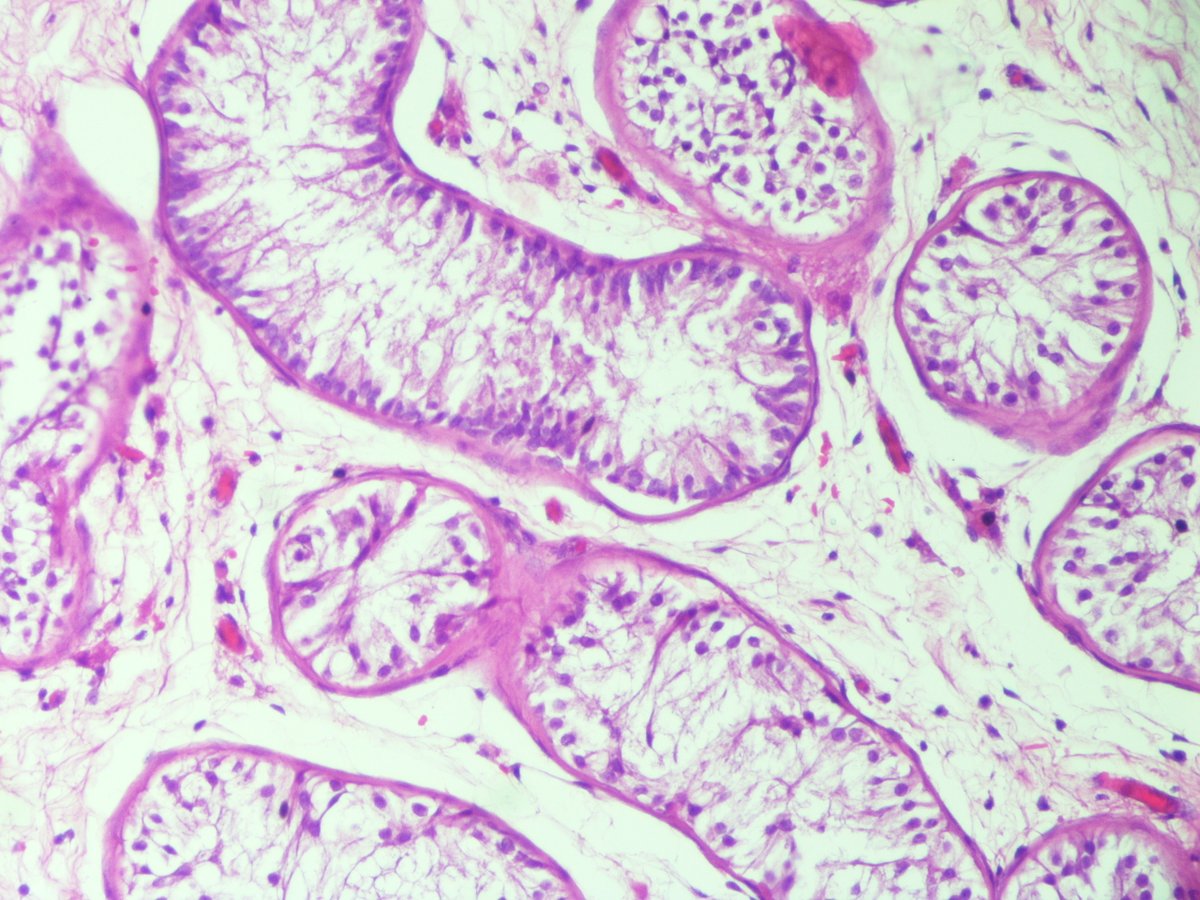

🔬 Renal Tubular Atrophy ~ Tubules with wrinkled and thickened basement membranes and reduced luminal areas ~ #RenalPath #Pathology #Kidney